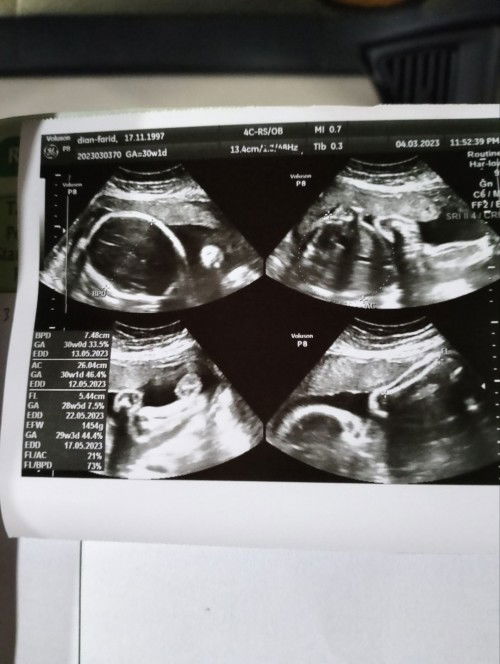

Bayi Sungsang dan berat badan baru 1 kg. Di Usia Kehamilan 30week

UK 30 week 2 hari. Hasil USG semalam bayi Masih Sungsang posisi kepala diatas kaki di bawah dan berat bayi juga masih 1kg.. bagi tips dan cara supaya debaynya cepat putar posisi dan berat bayi bisa bertambah di dalam rahim bundaa 🙏🙏🙏 #seriusnanya #bantusharing #ingintahu #pleasehelp